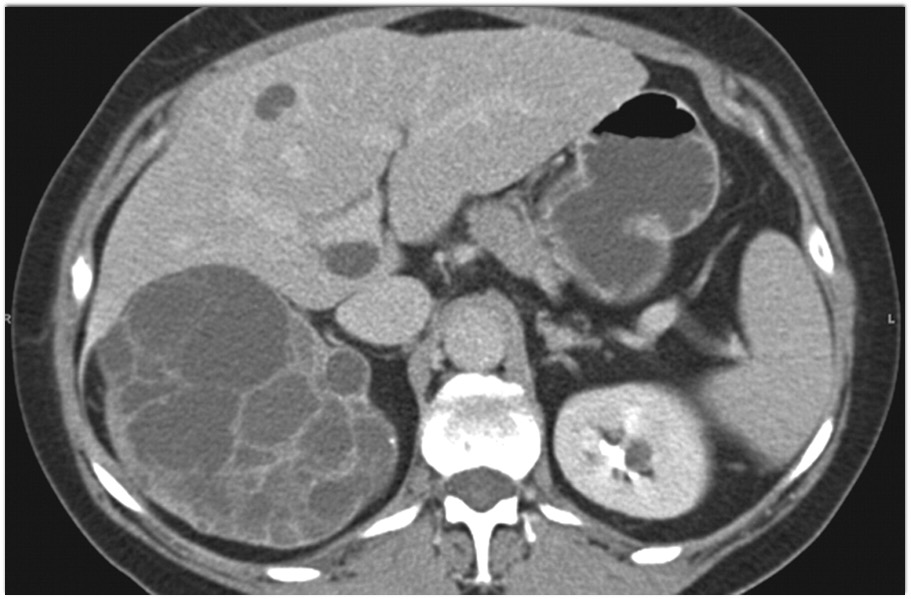

9) The best diagnosis in this 30ish year old female is?

renal cell carcinoma

MEST tumor (mixed epithelial and stromal tumor)

Wilms tumor

polycystic kidney disease